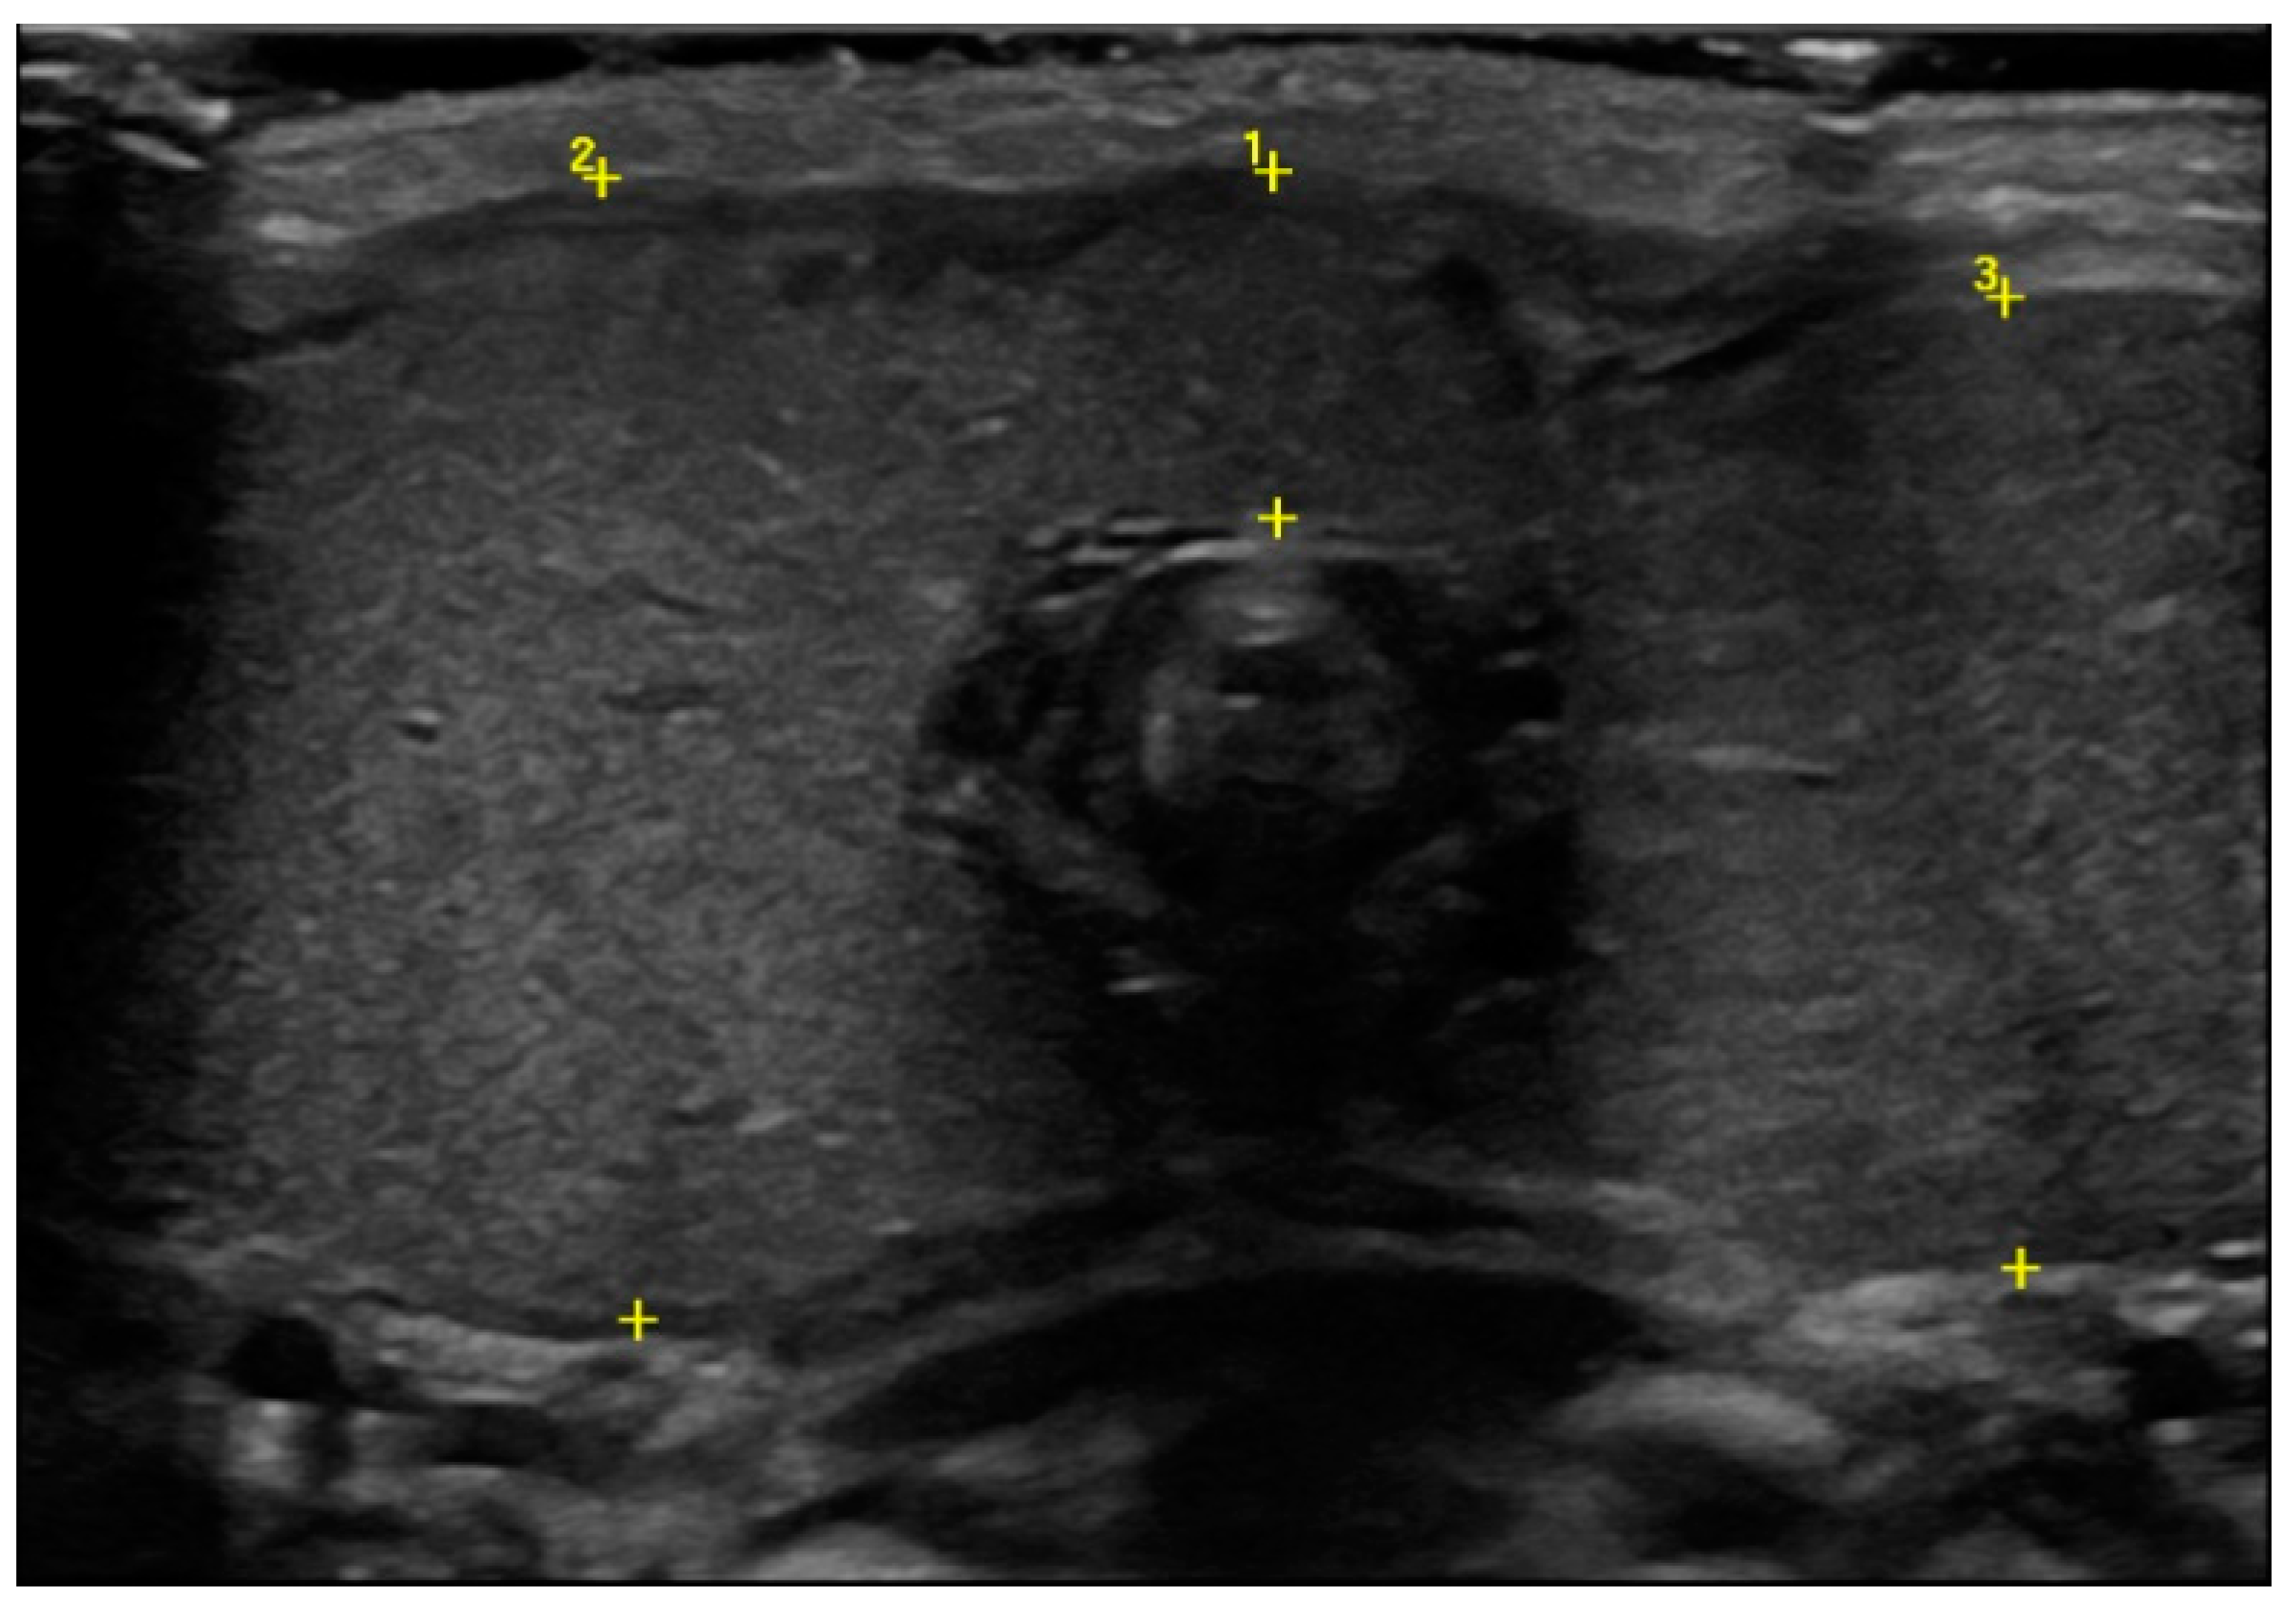

Ultrasound showed an enlargement of the thyroid gland (antero–posterior diameter of the right lobe was 2.5 cm and the left one was 2.2 cm, Figure 2), with a normal echogenic pattern and increased blood flow with central vascularization.

Figure 2.

Thyroid ultrasound at birth in which the enlargement of the gland was detected (cursor 1 isthmus, 0.8 cm; cursor 2 antero–posterior diameter of the right lobe, 2.5 cm; cursor 3 antero–posterior diameter of the left lobe, 2.2 cm).